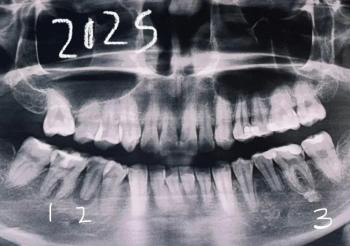

Scale All Teeth

Upper and lower teeth visible